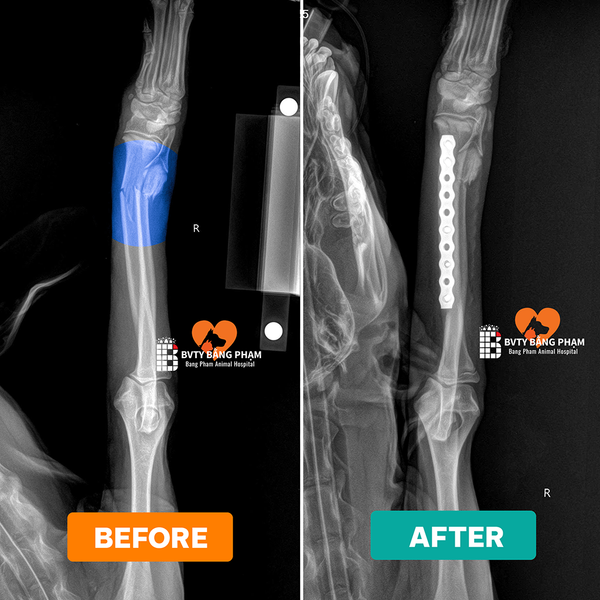

- Chụp X-quang (X-ray) để xác định chính xác vị trí và loại gãy xương (type of fracture).

- Nhấn mạnh: Phẫu thuật chỉnh hình xương (orthopedic surgery) đòi hỏi trang thiết bị chuyên biệt (thiết bị cố định bên trong/bên ngoài – internal/external fixation) và bác sĩ chuyên khoa.

Tại Bệnh viện thú y Bằng Phạm, đội ngũ bác sĩ chuyên khoa Ngoại – Chỉnh hình của chúng tôi sở hữu nhiều năm kinh nghiệm trong điều trị và phẫu thuật gãy xương cho chó mèo, bao gồm cả những ca phức tạp như gãy hở, gãy nhiều đoạn, hay trật khớp đi kèm tổn thương phần mềm.

Các bác sĩ đều được đào tạo chuyên sâu về phẫu thuật xương khớp và phục hồi chức năng thú y, với chứng chỉ BlueSAO quốc tế uy tín.